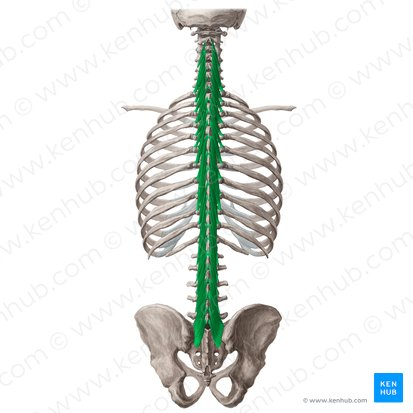

Iliocostalis

Hållning

mm longissimus

Hållning

mm spinalis

Hållning